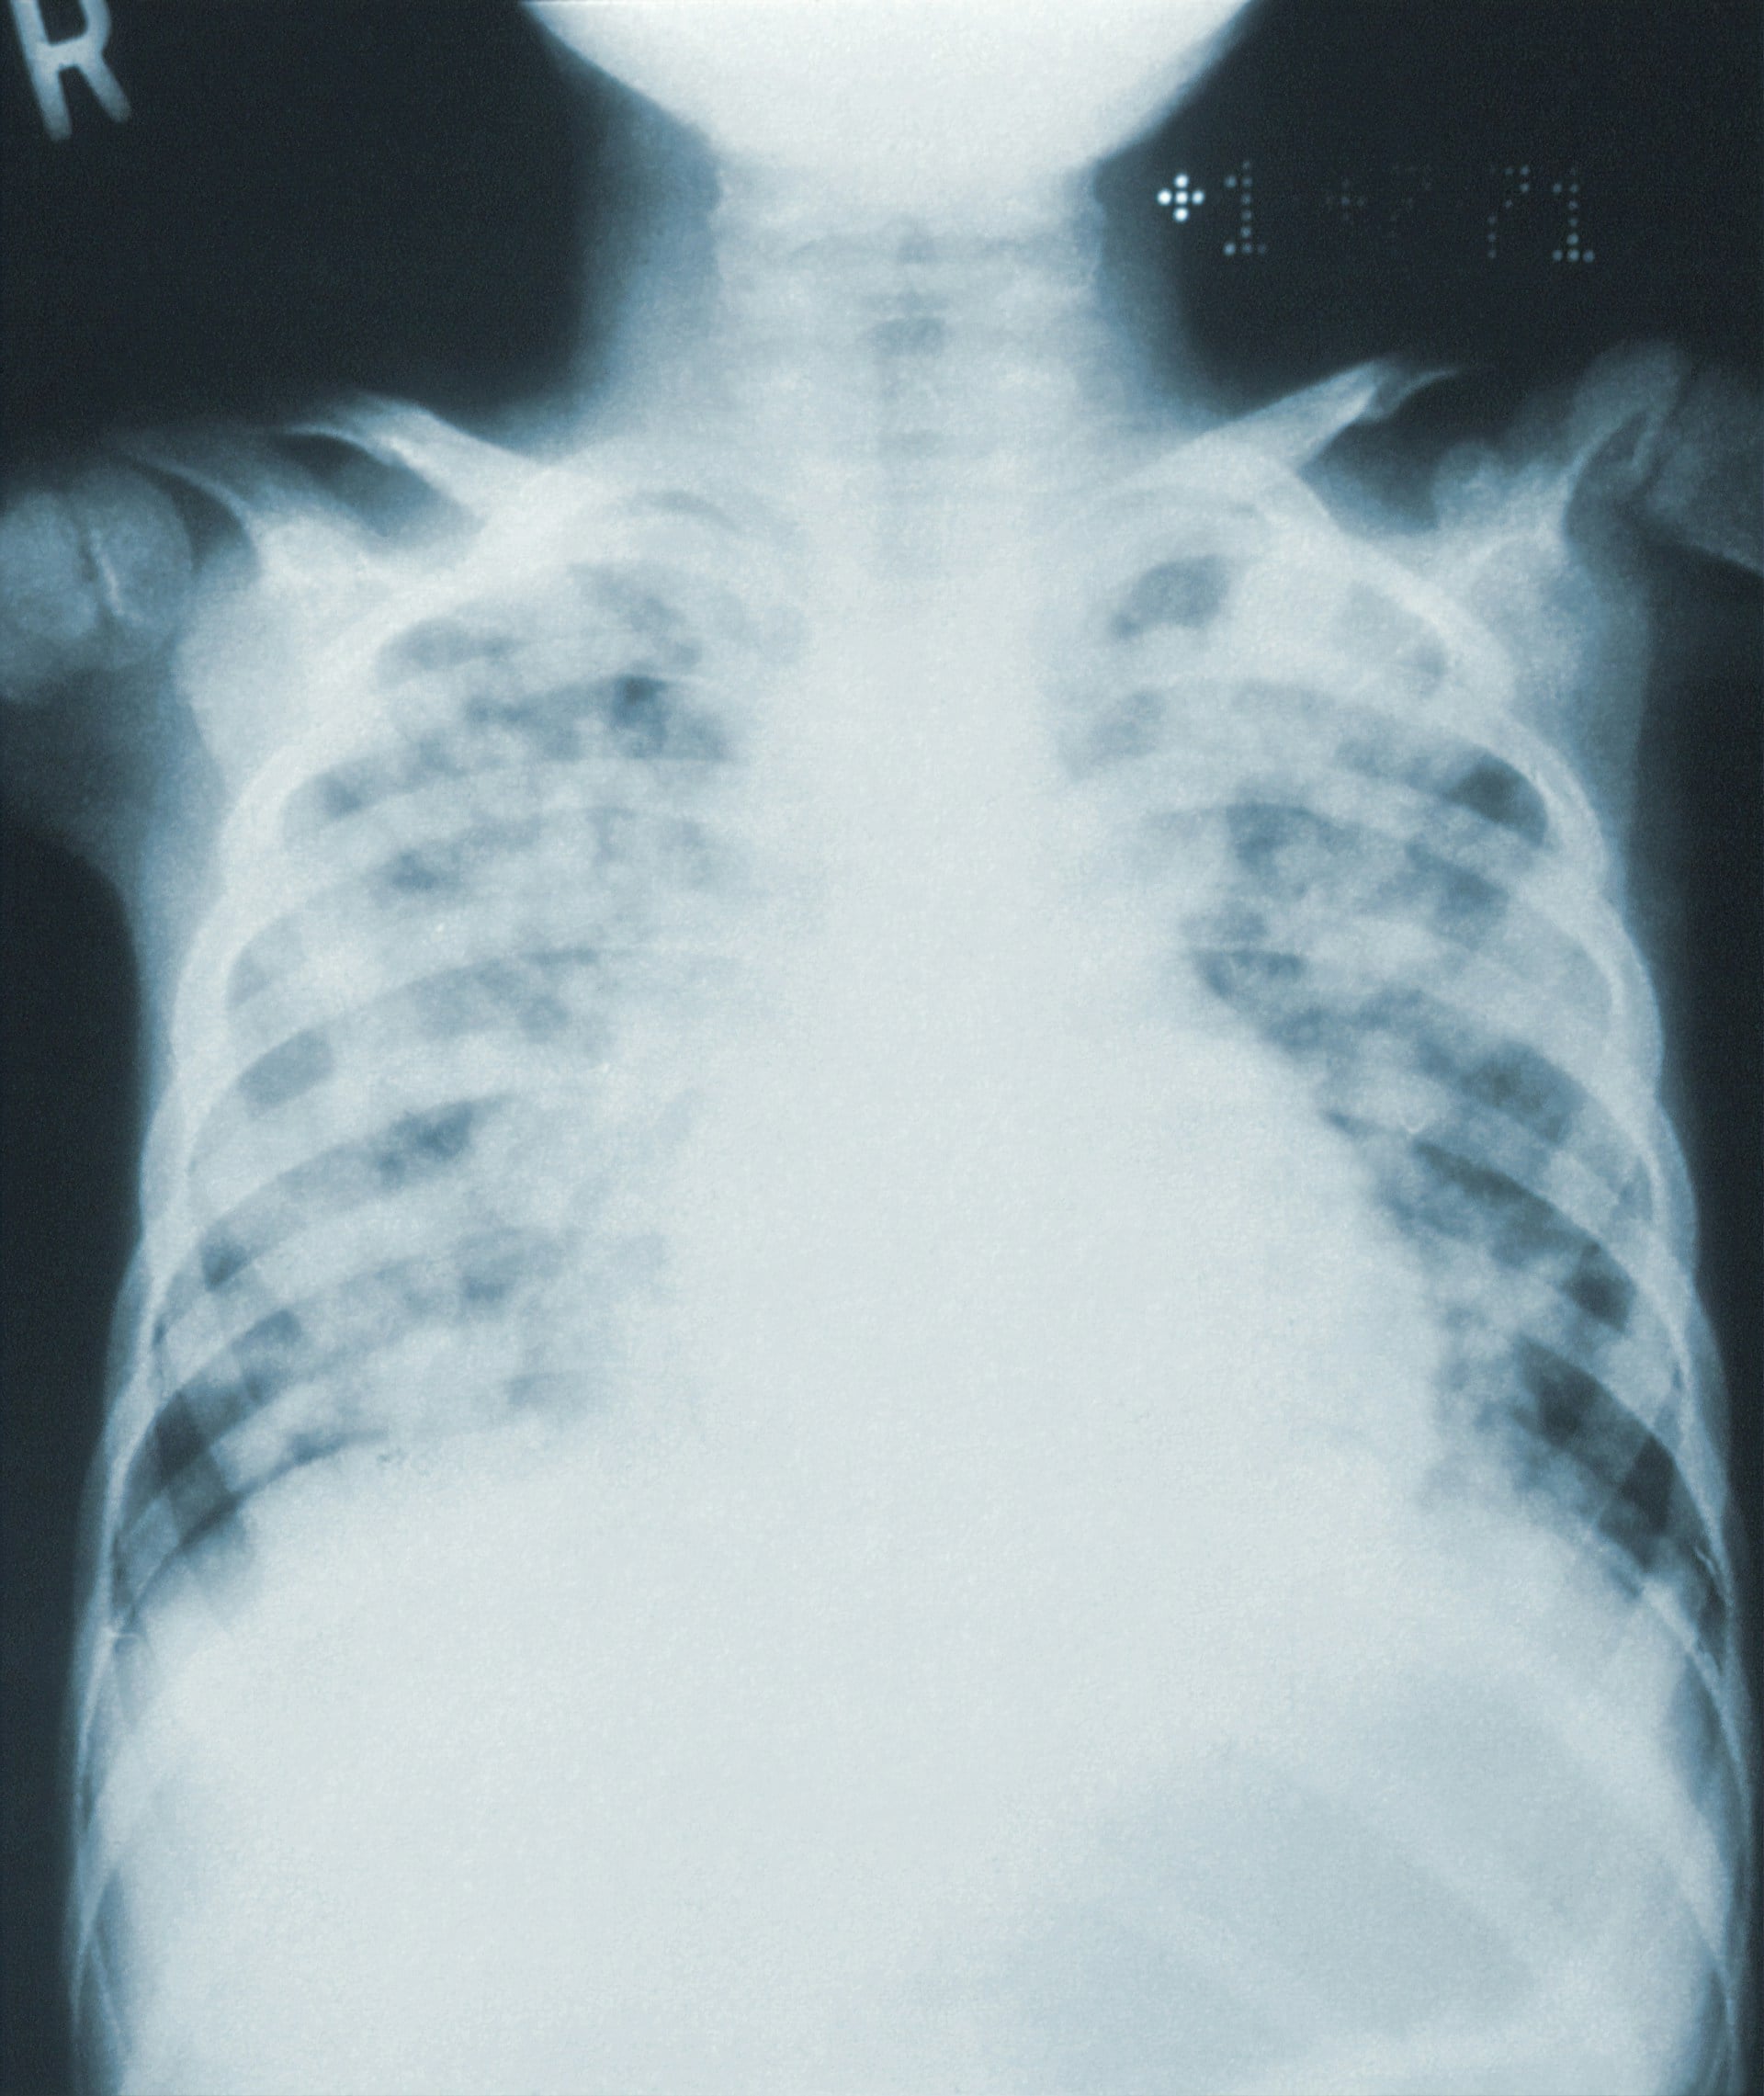

Those who test positive must undergo a chest X-ray screening, and may do so at the same location from 14 May to 15 May.

Cases whose X-rays are normal are deemed to have latent TB infection and will be offered preventive treatment to reduce the risk of developing active TB.

Persons with an abnormal X-ray will be evaluated at the National Tuberculosis Care Centre and start treatment if diagnosed with active TB.